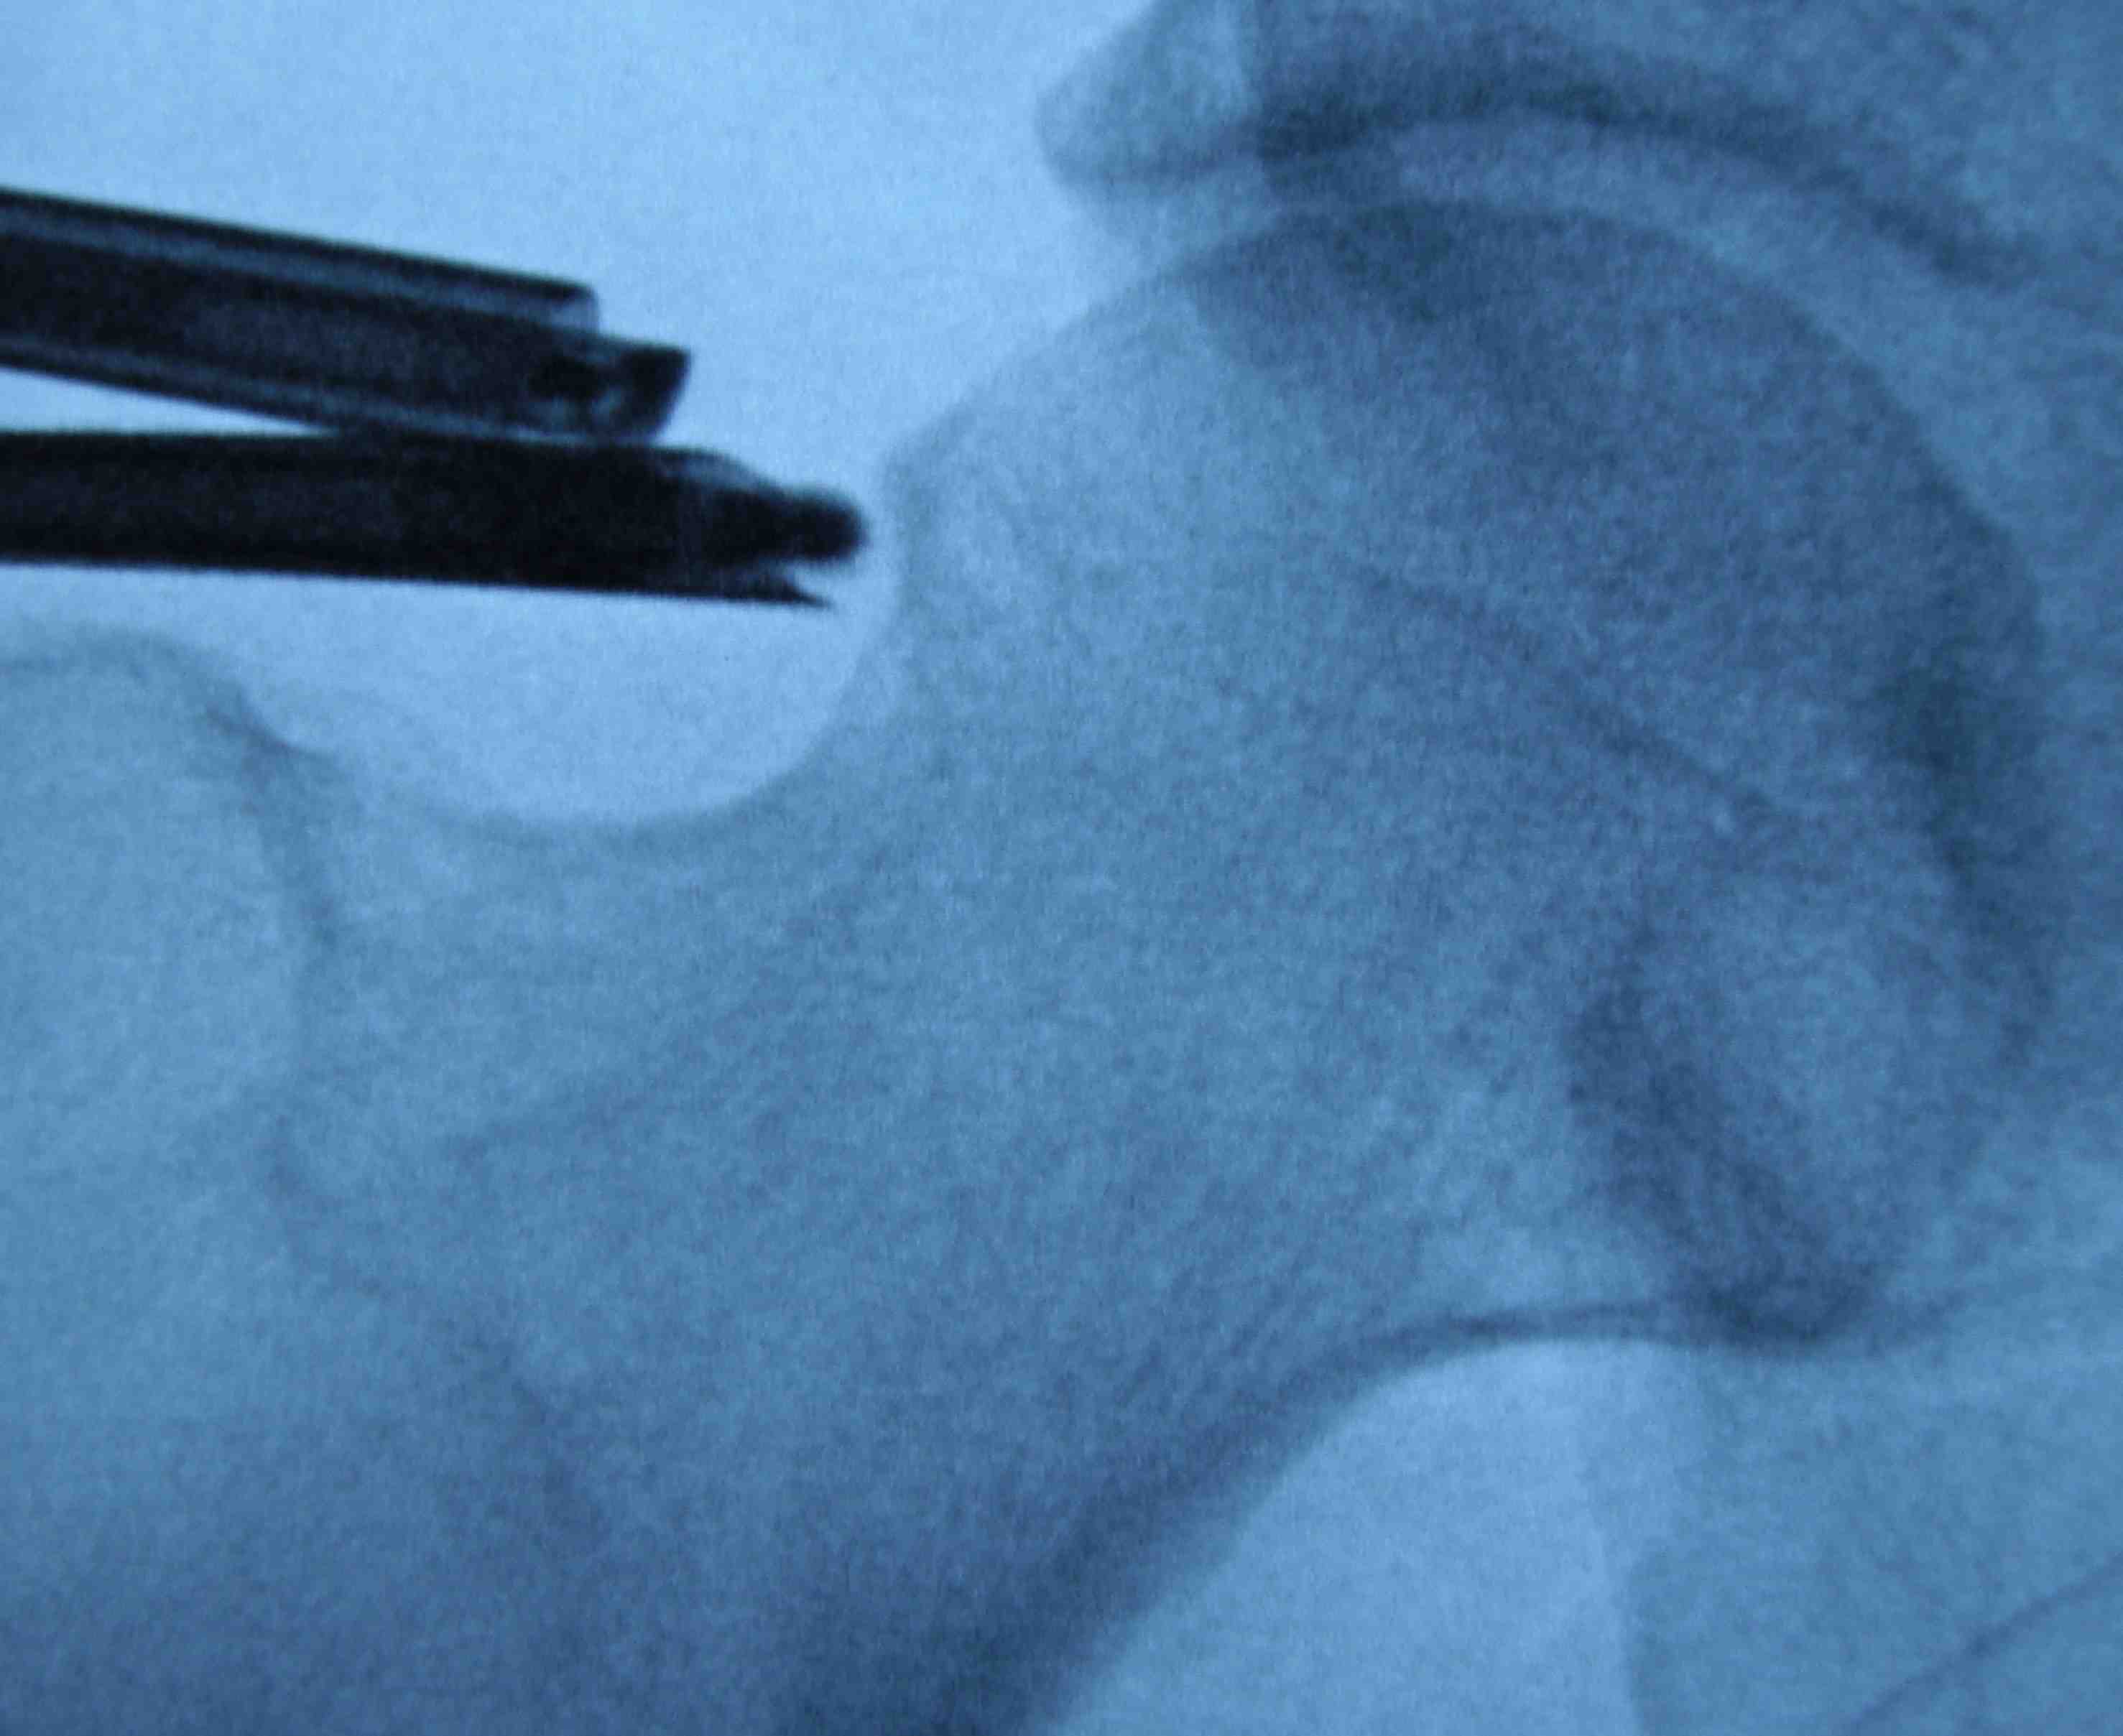

Anterior cam resection with hip flexed

Intra-operative Cam resection using Dunn view